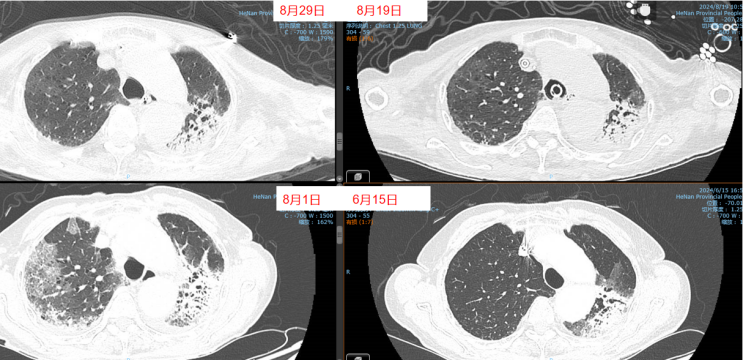

经过上述治疗,患者WBC、CRP、LDH、PCT均逐渐下降,肌酐正常。8月10日检查:WBC 9.1×109/L,CRP 6.8 mg/L,PCT 0.04 ng/ml,LDH 406 U/L。8月3-10日期间,患者心率持续变快,需要两种血管活性药物控制血压,无法进行俯卧位通气。ECMO上机前,患者右肺渗出性病变明显加重(图3)。

8月11日呼吸机吸氧浓度40%,ECMO气浓度约为80%,持续3天,激素减量氧合恶化,因心脏问题不能俯卧位通气(心率快,应用艾司洛尔及胺碘酮控制心室率)。气道分泌物不多,炎症指标正常。心脏问题,快速性心律失常,请心内科专家会诊,考虑舒张功能障碍,建议盐酸地尔硫卓联合胺碘酮控制心室率,血压低考虑可能血管张力问题,为减轻去甲肾上腺素对心脏的刺激,调整间羟胺维持血压。6月26日用抗肿瘤靶向药物后,8月1日肺部CT,双肺病变明显加重,肿瘤进展还是感染诱发?或是肿瘤靶向药物引起的免疫相关性肺损伤?下一步怎么办?肿瘤靶向药物还能用吗?8月11日请詹庆元教授会诊,考虑肿瘤靶向药物引起间质性肺炎可能性大,甲强龙80 mg q12h;心内科建议倍他乐克6.25 mg q12h口服联合盐酸地尔硫卓控制心室率;间羟胺替换去甲肾上腺素。8月12日心率65~85次/分,俯卧位8小时,白天ECMO 80%下调60%。患者氧合持续好转,随着病情好转,抗生素降阶梯治疗。8月13日,BALF涂片发现大量白细胞,以及多种形态阴性杆菌,像洋葱伯克霍尔德菌和伊丽莎白菌。8月14日,tNGS结果回报按蚊伊丽莎白菌、洋葱伯克霍尔德菌和脓肿分枝杆菌。据此调整抗感染药物:磺胺2片tid,多黏菌素E,美罗培南,利奈唑胺,伏立康唑。8月20日撤离ECMO。8月21日,病原学提示脓肿分枝杆菌进行性增多,加用左氧氟沙星。8月26-28日尝试甲强龙减量(60 mg→40 mg),患者再次再次出现氧合变化,未能成功转换为无创通气,有创通气PS降至8 cmH2O,PEEP 5 cmH2O。复查胸部CT,发现右肺渗出性病变再次出现。8月29-30日,甲强龙剂量调整为80 mg。8月31至9月3日,甲强龙剂量调整为60 mg。8月27日复测tNGS,回报木糖氧化无色杆菌(序列数47605),人类疱疹病毒1型(序列数176998),按蚊伊丽莎白菌、洋葱伯克霍尔德菌和脓肿分枝杆菌序列数较前减少。细菌室回报木糖氧化无色杆菌。患者出现了一些不良反应,包括骨髓抑制,纤维蛋白原、血小板、血红蛋白、白细胞、淋巴细胞数都在降低。考虑可能是磺胺药物和利奈唑胺引起,所以停用这两种药物。调整抗感染药物:阿米卡星雾化,左氧氟沙星,多西环素,伏立康唑,阿昔洛韦。之后由于不良反应,8月31日停用了左氧氟沙星和多西环素。9月3日查血,患者血小板升高。如下图所示,6月15日为抗肿瘤药物使用前,8月1日为抗肿瘤药物使用后,8月19日第一次复查CT,激素减量后,8月29日再次复查CT,右肺渗出性病变较前明显增多(图4)。

图4 患者影像学变化

患者存在两大问题,一是撤机困难,二是肌无力。后续复查影像学发现右肺斑片渗出逐渐好转,积极进行四肢肌力和膈肌的康复治疗。